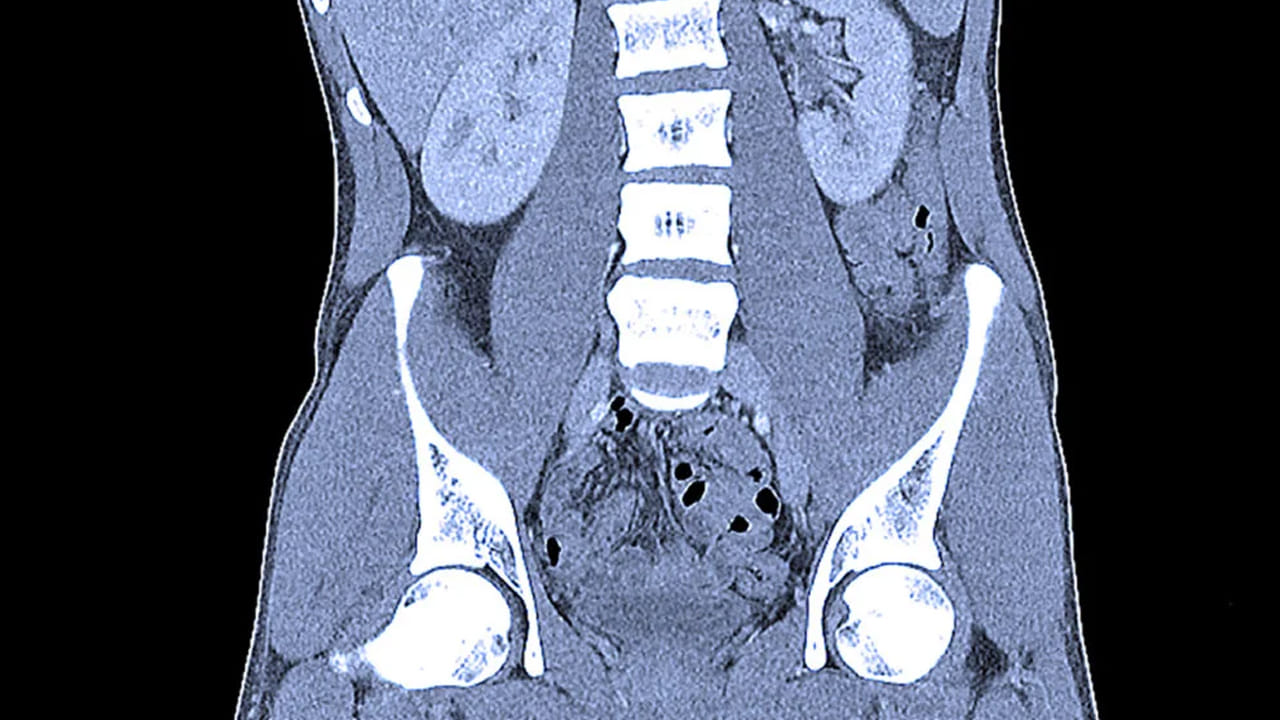

శ్రీ సత్యసాయి జిల్లా ధర్మవరంలో విచిత్ర ఘటన వెలుగుచూసింది. పట్టణంలోని రాజేంద్రనగర్కు చెందిన రామాంజనేయులు అనే వ్యక్తి గత కొన్ని రోజులుగా కడుపు నొప్పితో తీవ్ర అస్వస్థతకు గురవుతున్నాడు. తెలిసిన ఆర్ఎంపీ వద్ద మందులు వాడుతున్నా కూడా ప్రయోజనం లేకపోయింది. అయితే ఇటీవల ఉన్నఫలంగా మాట్లాడలేని స్థితికి చేరుకున్నాడు. దీంతో కంగారుపడ్డ కుటుంబ సభ్యులు ప్రవేట్ ఆస్పత్రికి తీసుకెళ్లారు. అక్కడ టెస్టులు చేసి డాక్టర్లు.. రిపోర్టులు చూసి స్టన్ అయ్యారు. అతడి కడుపులో గొలుసు ఉన్నట్లు గుర్తించారు. ఏంటా అని ఎంక్వైరీ చేయగా అది అతని భార్య బంగారపు నల్లపూసల గొలుసు అని తేలింది.

ఆపరేషన్ చేసి.. ఆ చెయిన్ బయటకు తీయాలిని ఆ ఆస్పత్రి వైద్యులు చెప్పారు. అంత డబ్బు పెట్టే స్థోమత లేకపోవడంతో… బాధితుడ్ని ప్రభుత్వ ఆస్పత్రికి తీసుకెళ్లారు. అక్కడ ఎలాంటి ఆపరేషన్ లేకుండా.. నోటి ద్వారా చెయిన్ బయటకు తీశారు ప్రభుత్వ ఆస్పత్రి వైద్యులు డాక్టర్ సుకుమార్. దీంతో బాధిత కుటుంబ సభ్యులు డాక్టర్లకు ధన్యవాదాలు తెలిపారు. అయితే అతడు గొలుసు ఎందుకు మింగాడు అన్నది తేలాల్సి ఉంది. మానసిక స్థితి బాలేదా..? లేదా చెయిన్ కొట్టేసే క్రమంలో మింగేశాడా అన్న విషయంలో బాధితుడు రికవరీ అయ్యి.. కాస్త మాట్లాడే శక్తి వచ్చాక స్పష్టత వచ్చే అవకాశం ఉంది.